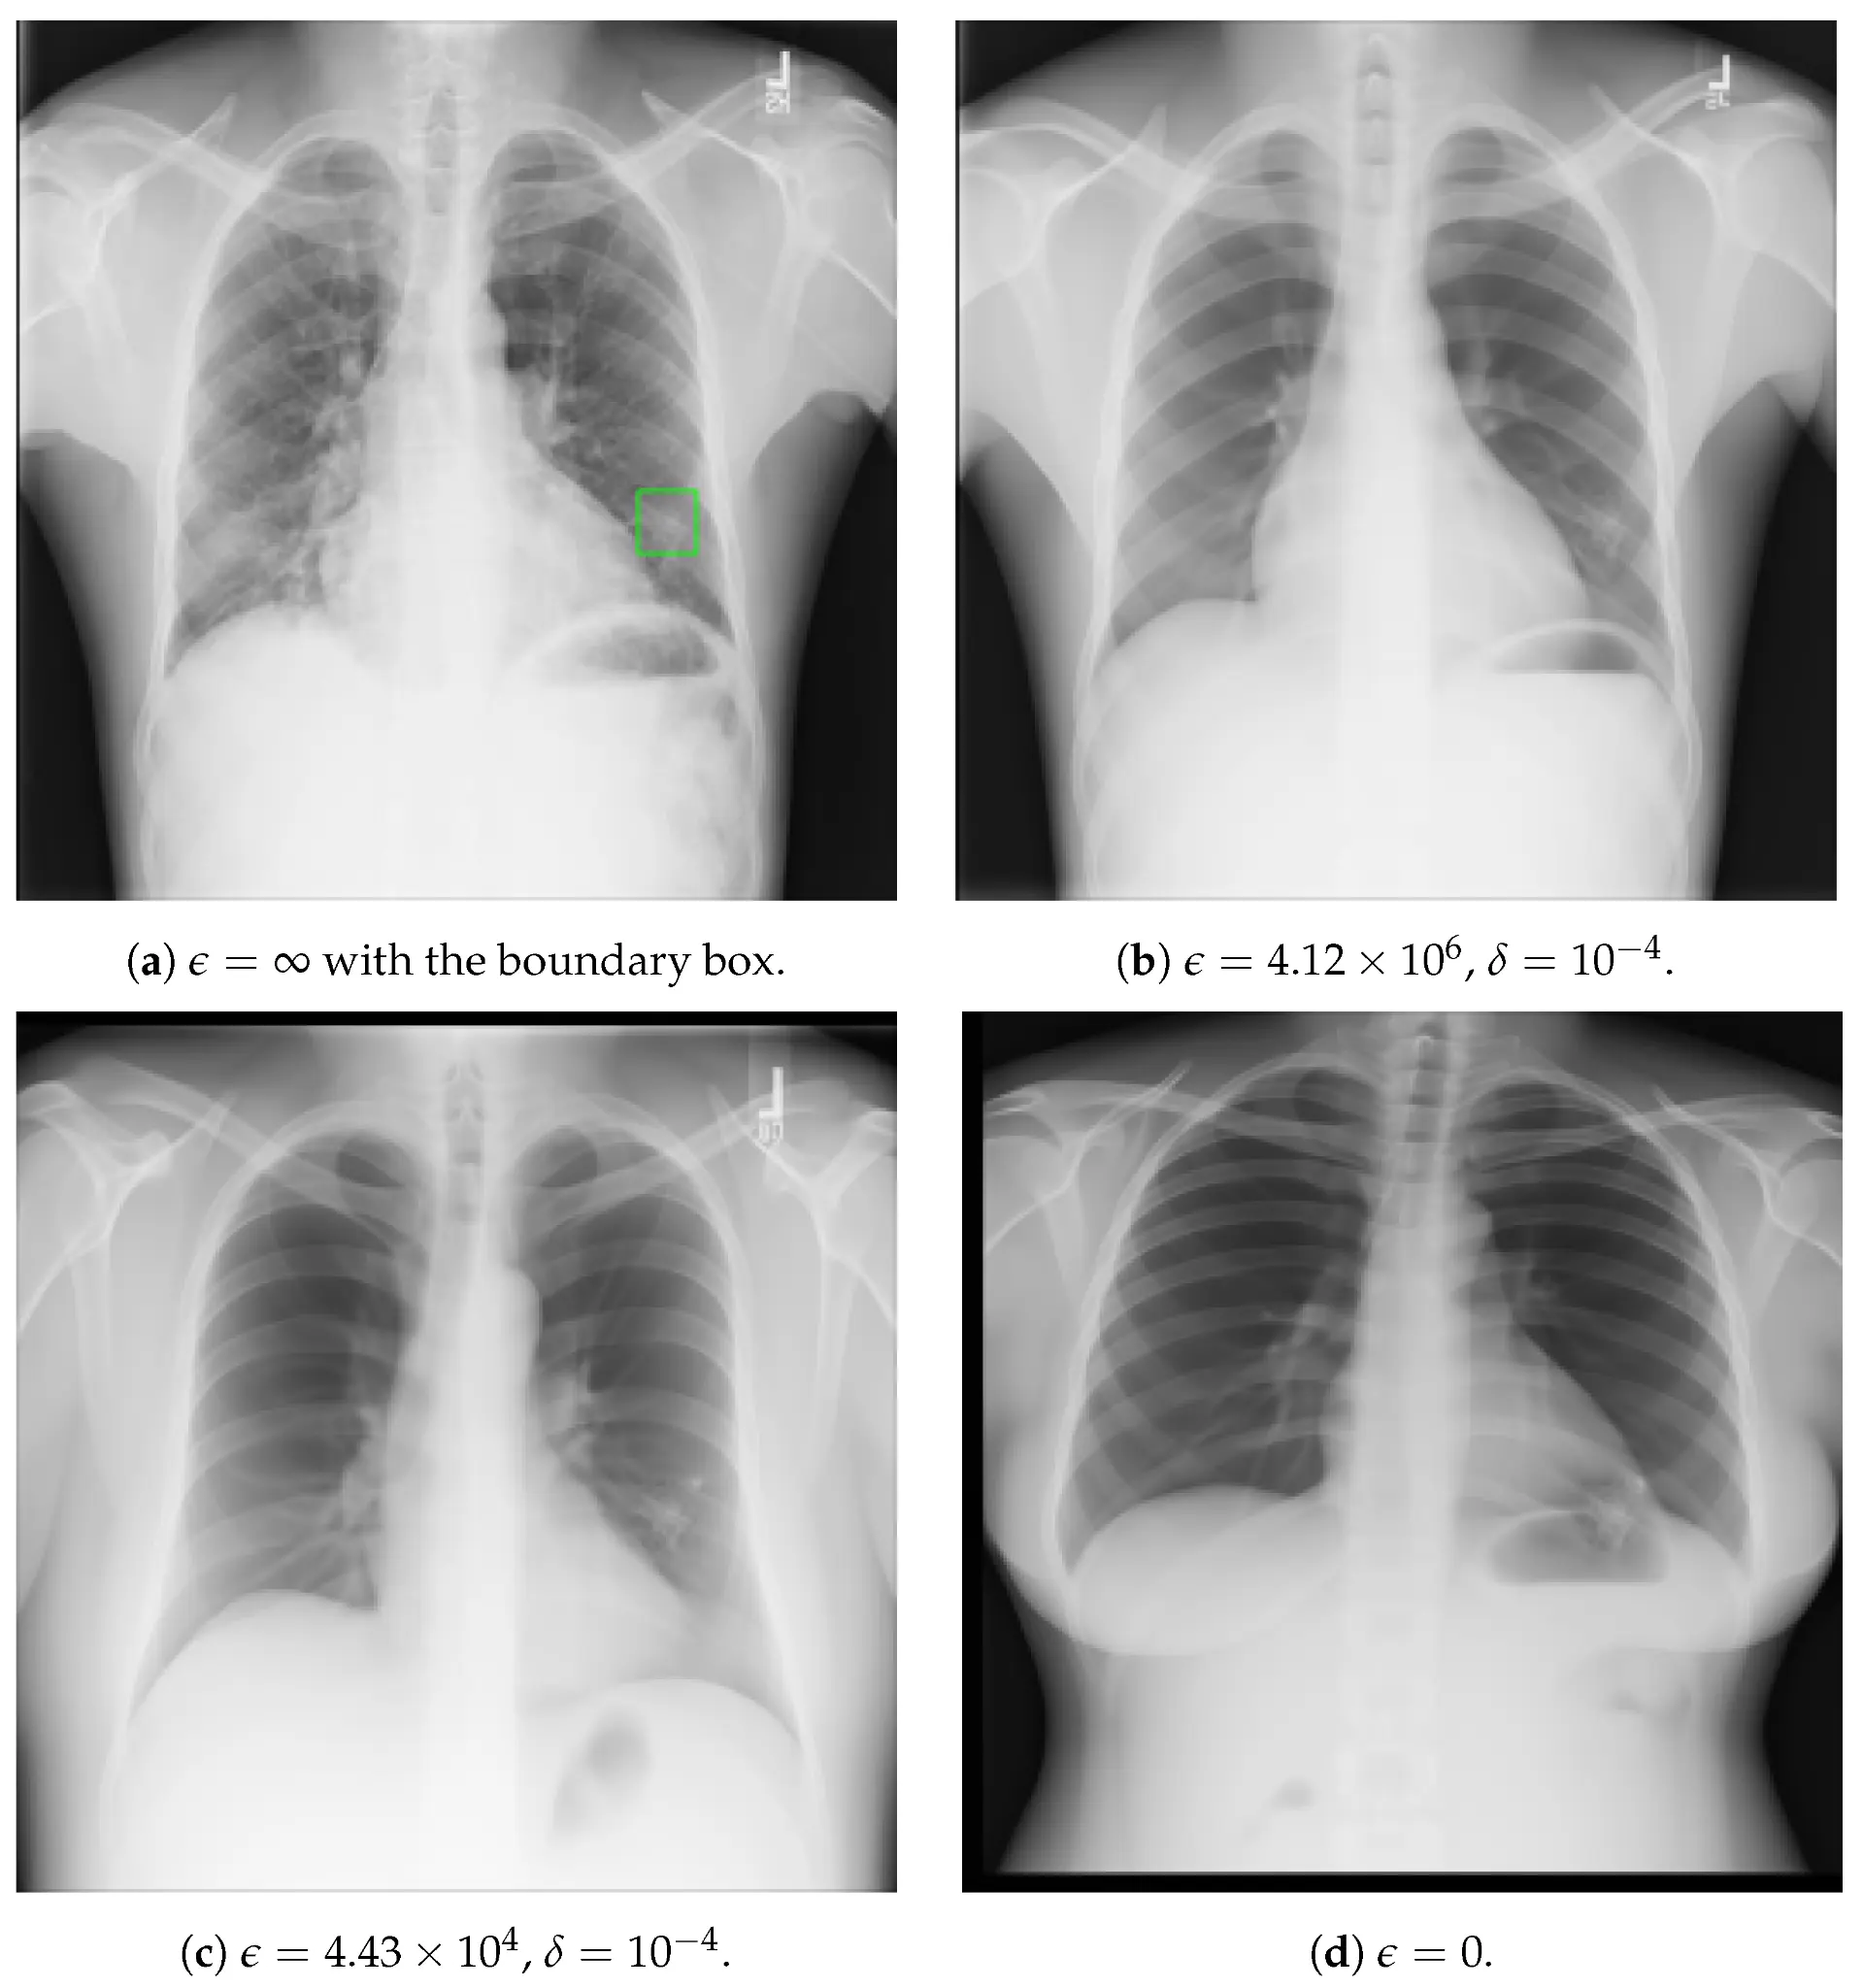

差分プライバシー

画像から疾患を消さず個性を消す